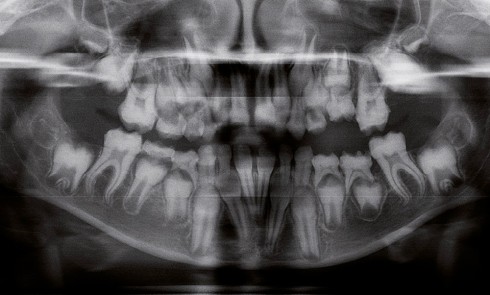

Article réservé à nos abonnés Les amélogenèses et dentinogenèses imparfaites : classifications clinico-moléculaires, aspects histologiques, cliniques et radiologiques

Une pathologie est dite rare lorsqu’elle affecte moins d’un individu sur 2 000 dans une population. Les amélogenèses imparfaites héréditaires (AIH)...